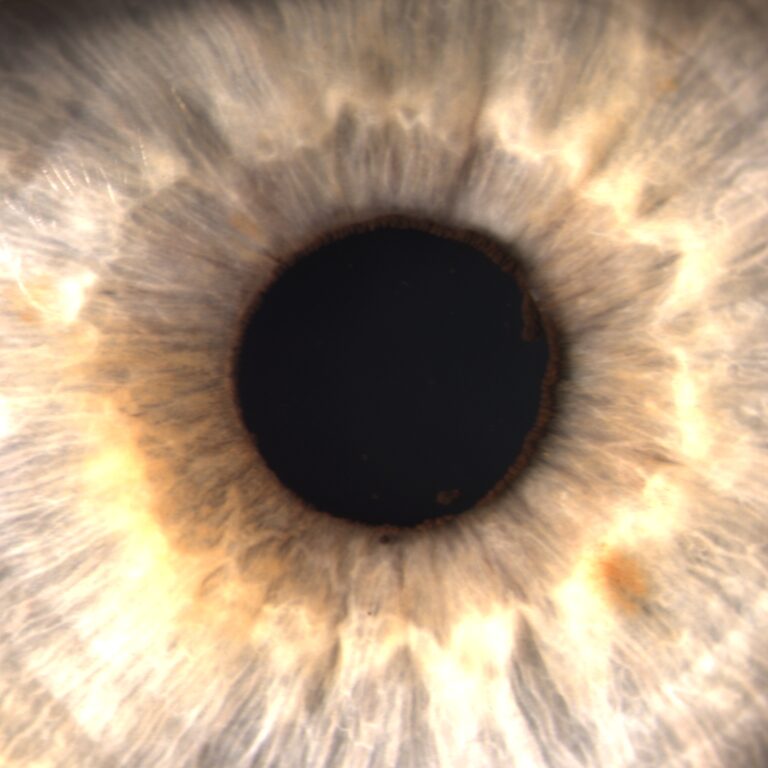

Slit lamps (H-style and Z-style)

Table-top and portable, for detailed anterior and posterior segment examination.

Featured image: Iris images taken with a Keeler slit lamp. Photo credit: Hamza Mussa, aka @TheCrazyOptom